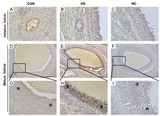

[초록] 여름철 열 스트레스와 국내 모돈 난소에서의 카스파제-3 활성화 관계